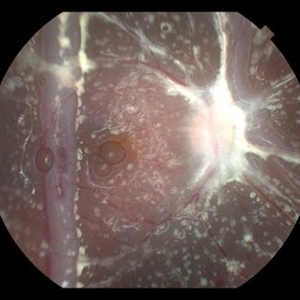

Fundus photograph of a 15-year-old boy post cataract aspiration, pars plana vitrectomy, suprachoroidal drainage, and retinal reattachment surgery secondary to traumatic endophthalmitis.

Condition/keywords: endophthalmitis, PFCL, Retinal detachment under Silicon Oil, retinal fold